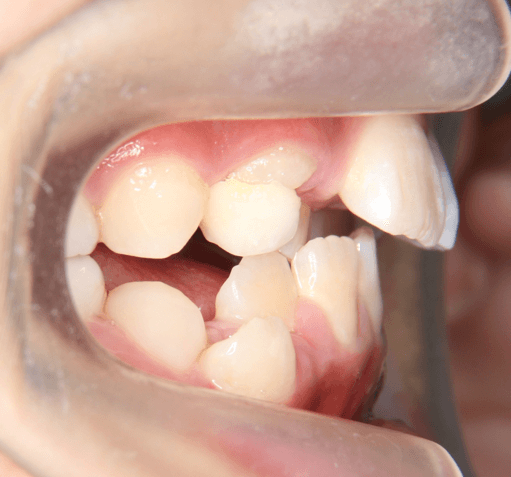

| 年齢・性別 | 男性 |

|---|---|

| 主訴 | 上の永久歯の前歯が1本だけ後ろに生えてしまった |

| 治療期間・回数 | 4ヶ月 |

| 費用 | 330,000円(税込) |